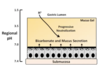

What are the 2 stages of saliva production, which include exocrine secretion and funneling of secretions?

1 - acinar phase (secretion of exocrine secretions)

2 - duct phase (exocrine secretions move into oral cavity)

In the first phase of saliva production, called acinar phase, which electrolytes are high in concetration, and what follows these?

- Na+

- Cl-

- H2O always follows Na+